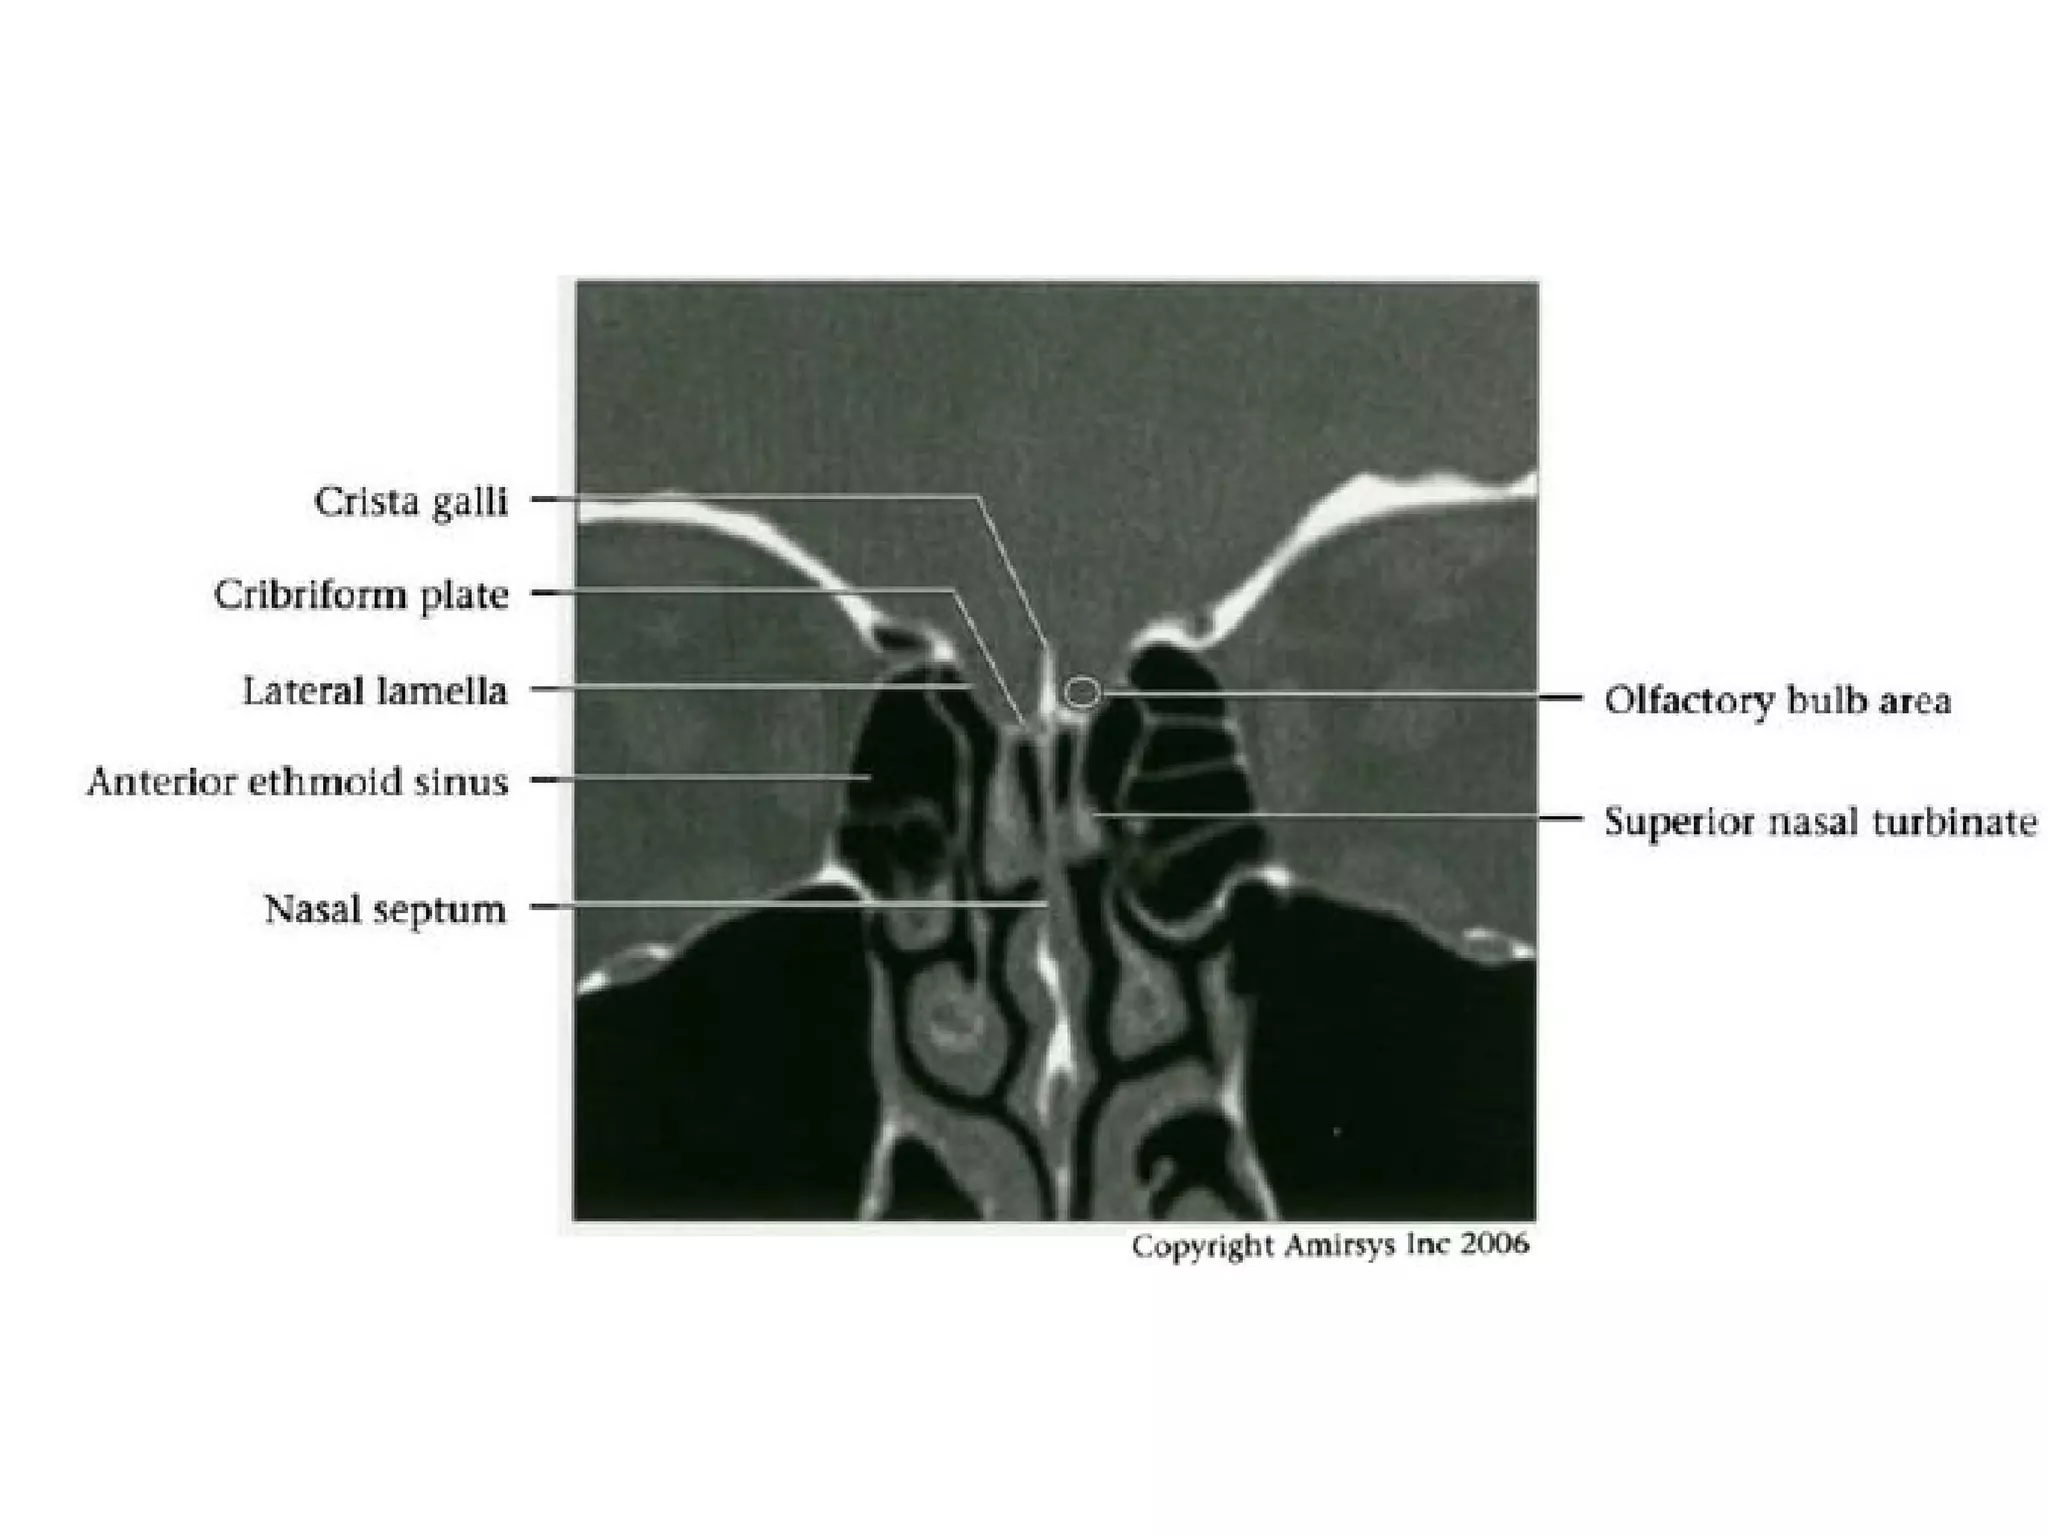

CN1: Nasal Epithelium

• Approximately 2 cm² nasal epithelium in roof of each

nasal cavity

- Extends onto nasal septum and lateral wall of nasal

cavity including superior turbinates

CN1: Transethmoidal Segment

• Central processes of bipolar receptor cells

traverse cribriform plate to synapse with

olfactory bulb

• Hundreds of central processes traverse

cribriform plate as unmyelinated fascicles

(fila olfactoria)

- Fila olfactoria are actual olfactory nerves

- Each side of nasal cavity has - 20 fila

olfactoria

CN1: Imaging Recommendations

• Coronal sinus CT is best study for isolated

anosmia

- Identifies nasal vault and cribriform plate

lesions

CN1: Imaging "Sweet Spots"

• Intracranial: Include anterior cranial fossa

floor and medial temporal lobes

• Extracranial: Include nasal vault and

cribriform plate

• Unlike most cranial nerves, the olfactory nerve consists

of white-matter tracts and is not surrounded by Schwann

cells

• The neurosensory cells for smell reside in the olfactory

epithelium along the roof of the nasal cavity

• The axons of these cells extend through the cribriform

plate of the ethmoid bone into the olfactory bulb at the

anterior end of the olfactory nerve

• The nerve then courses posteriorly through the anterior

cranial fossa in the olfactory groove

• Posterior to the olfactory groove, the cisternal segment

of the nerve runs below and between the gyrus rectus

and the medial orbital gyrus

Cranial Nerve I:

The Olfactory Nerve

• These secondary axons in the olfactory nerve

eventually terminate in the inferomedial temporal

lobe, uncus and entorhinal cortex

• To avoid confusing the olfactory nerve with the

gyrus rectus on axial images, it is important to

remember that the olfactory nerve is situated

deep in the olfactory groove, inferior to the gyrus

rectus

• Coronal images are easiest to interpret because

the nerves are seen in cross section

RadioGraphics 2009; 29:1045–1055